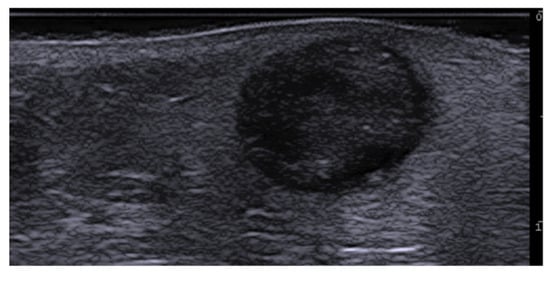

- Li, L.; Xu, J.; Wang, S.; Yang, J. Ultra-High-Frequency Ultrasound in the Evaluation of Paediatric Pilomatricoma Based on the Histopathologic Classification. Front. Med. 2021, 8, 673861. [Google Scholar] [CrossRef]